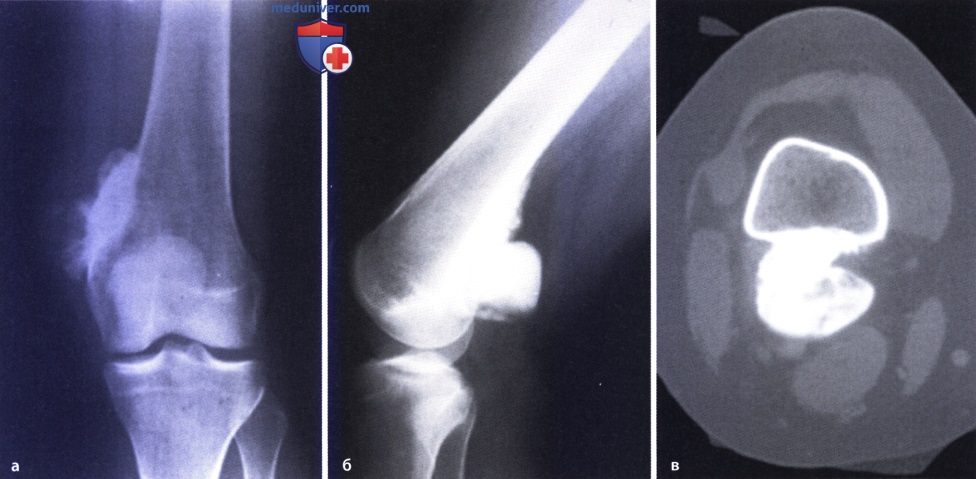

Остеосаркома коленного сустава: информация и поддержка

Раздел: Необычные решения